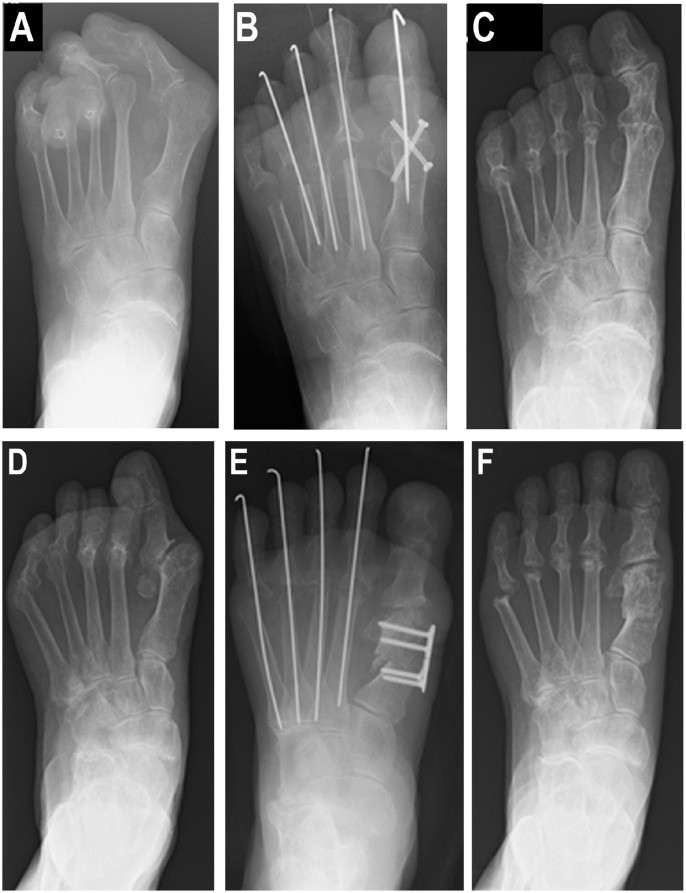

Methods: This single-center retrospective study at Kyushu University Hospital reviewed RA patients who underwent either first MTP joint arthrodesis or joint-preserving surgery for hallux valgus (HV) deformity between January 2008 and December 2022. A total of 103 feet (73 cases) were analyzed, with 75 feet (58 cases) showing radiographic bone destruction of Larsen grade 3 or higher. One foot underwent resection arthroplasty, so ultimately 74 feet in 57 cases were evaluated. Surgical procedures included joint-preserving biplane osteotomy or arthrodesis with crossed screws. Clinical outcomes were measured using the Japanese Society for Surgery of the Foot (JSSF) Hallux scale, whereas radiographic assessments included HV angle (HVA). Propensity score matching was used to minimize bias when comparing postoperative outcomes between the arthrodesis and joint-preserving surgery groups.

Results: This study analyzed 74 feet undergoing either arthrodesis (27 feet) or joint-preserving surgery (47 feet) for HV. Patients in the 2 groups showed similar demographic and clinical characteristics except with respect to length of follow-up, which was greater in the arthrodesis group (5.1 ± 2.6 years vs 2.4 ± 2.0 years, P < .01) than the joint-preserving group. In the arthrodesis group, all patients underwent resection arthroplasty on the second to fifth toes. The joint-preserving group included first MTP joint surgery alone (n = 5) and first MTP joint and lesser MTP joint surgeries (resection arthroplasty, n = 29; joint-preserving surgery, n = 13). Functional scores significantly improved in both groups, with first metatarsophalangeal joint-preserving surgery yielding better postoperative outcomes. In cases of deformity recurrence, the recurrent cases exhibited greater immediate postsurgical HVA, but other foot function outcomes remained similar at the end of follow-up.